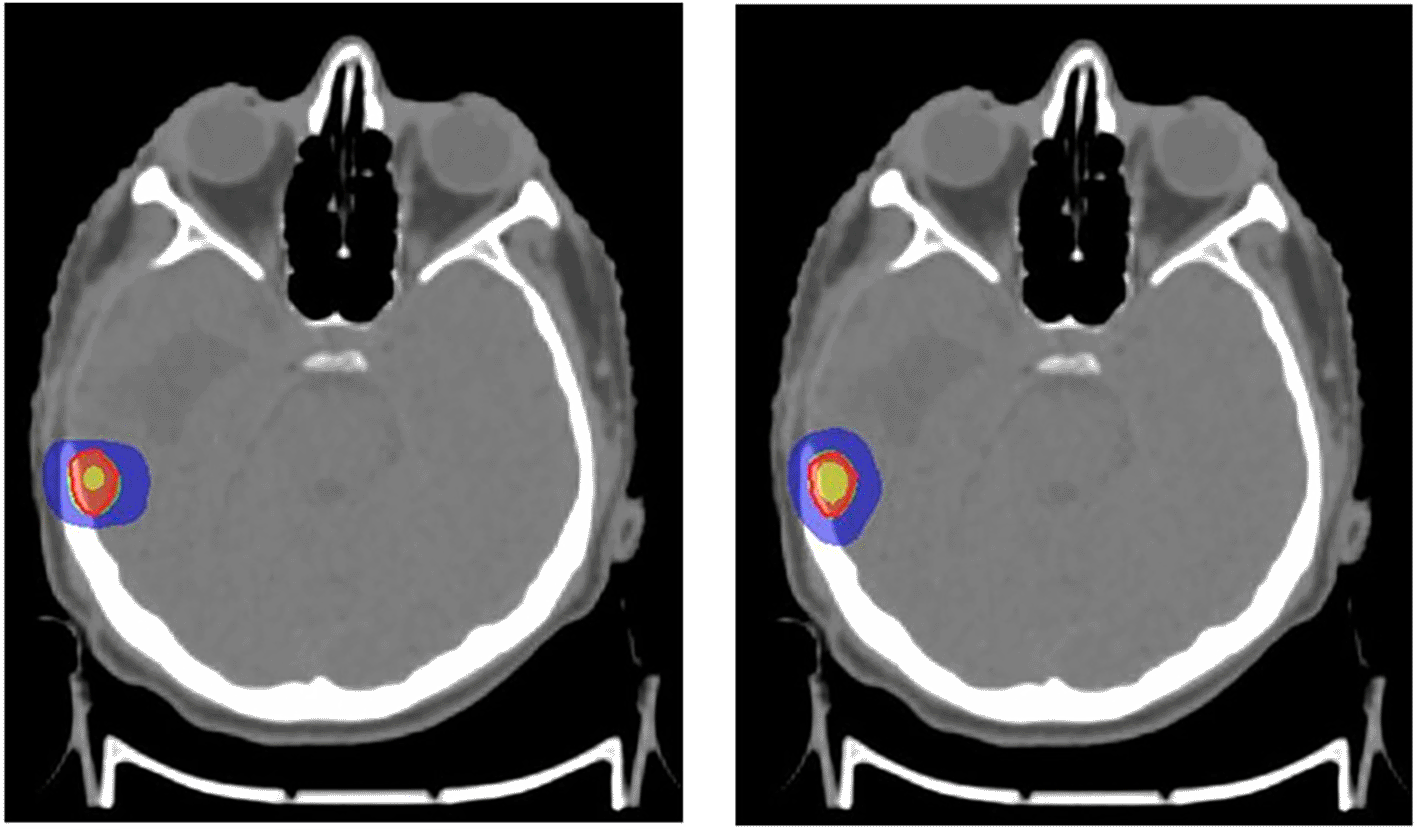

The first plan for SRS/SBRT was developed using the dynamic conformal arc therapy (DCAT) technique with a 6FFF photon beam energy using a 2.5 mm Apex mMLC. The Apex mMLC is an additional attachment to the collimator of the Elekta Versa high-definition LINAC consisting of an MLC with a 2.5 mm width at the isocenter. This high-resolution collimating device is especially used for SRS treatment delivery to facilitate conformal dose distribution around the tumor. The maximum field size provided by the mMLC is 12 × 14 cm2.25 The isocenter was placed at the center of the target volume. The number and direction of the arcs were chosen based on the location of the tumor. Couch movement was restricted in some cases, wherever it was practically impossible to move the gantry with the Apex to reduce the risk of collision of the gantry with the couch and patient. The second plan was generated without using Apex mMLC. The LINAC has an inbuilt MLC with a 5 mm width at the isocenter, which is also called Agility. The SRS/SBRT treatment plans in this case were performed with agility using a 6FFF photon beam energy. The treatment plan was implemented using the same gantry couch combinations. Multiple optimizations in both techniques were performed to achieve the prescribed tumor dose and to bring the dose to the OARs within the given limits. The Monte Carlo algorithm was used to calculate the dose distribution.26 For the included cases, SRS was planned with 16 Gy in one fraction (Figure 1) and SBRT with 60 Gy in five fractions (Figure 2).

Red: 100% prescribed dose; Green: 95% prescribed dose; Blue: 50% prescribed dose; Yellow: 115% prescribed dose.